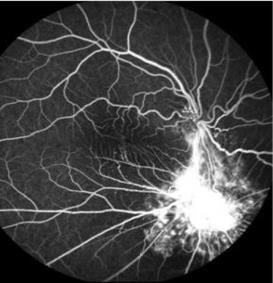

Ophthalmology | Dec 31, 2024

Comparative Safety and Effectiveness of Ranibizumab and Triamcinolone with Prompt Laser Treatment in Diabetic Macular Edema: A Systematic Literature Review and Meta-Analysis

Background: Diabetic macular edema (DME) can significantly hinder the life of many diabetic patients. Research has shown that intravitreal injections...Read More